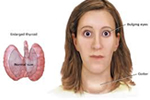

Hyperthyroidism

Hyperthyroidism

A Symdrome, when the secretion fom the thyroid glands is increased and which Overstimulates the basal metabolism.

A Symdrome, when the secretion fom the thyroid glands is increased and which Overstimulates the basal metabolism.

Hyperthyroidism, A Symdrome, when the secretion fom the thyroid glands is increased and which Overstimulates the basal metabolism.